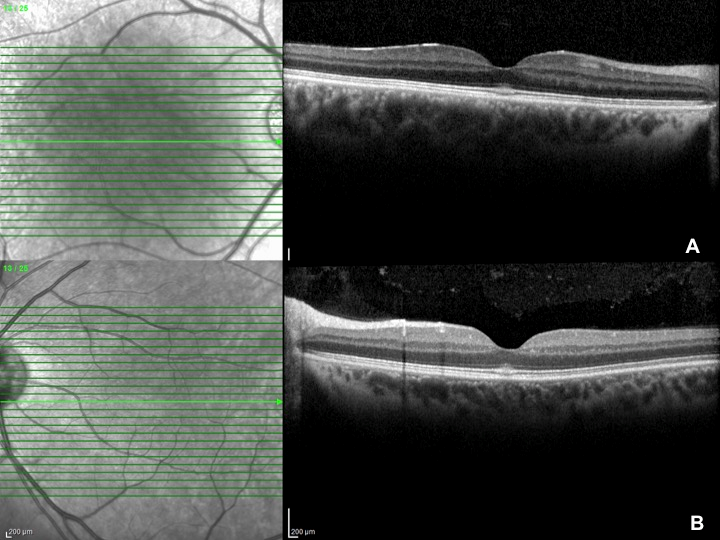

Best-corrected visual acuity was 0.9 and intraocular pressure was 16 mmHg in both eyes. Anterior segment was unremarkable. Fundus examination revealed hyperreflective appearence at macula with a faint foveolar reflex. OCT (Spectralis®, Heidelberg Engineering Inc., Heidelberg, Germany) demonstrated focal hyperreflectivity and irregularity of the ellipsoid zone at the fovea (Figure 1A,B [Fig. 1]). No other retinal abnormalities were found. FOF (short wavelength autofluorescence imaging, Heidelberg Spectralis) was normal (Figure 2A,B [Fig. 2]). OCTA (Avanti RT Vue XR® with AngioVue® software; Optovue Inc., Fremont, CA, USA) revealed no vascular changes (Figure 3A,B [Fig. 3]).

Figure 1: OCT demonstrates hyperreflectivity and irregularity of the ellipsoid zone at the fovea; A) OD, B) OS